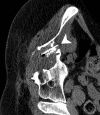

Materials and methods: In this HIPAA-compliant, institutional review board-approved prospective study with written informed consent, 25 patients (17 men, eight women) underwent 33 percutaneous and three intraoperative biopsies of 36 FDG-avid targets between November 2007 and August 2010. One patient underwent biopsy and RF ablation of an FDG-avid hepatic focus. Targets demonstrated heterogeneous FDG uptake or were not well seen or were totally inapparent at conventional imaging. Preprocedural FDG PET scans were rigidly registered through a semiautomatic method to intraprocedural CT scans. Coaxial biopsy needle introducer tips and RF ablation electrode guider needle tips containing electromagnetic sensor coils were spatially tracked through an electromagnetic field generator. Real-time US scans were registered through a fiducial-based method, allowing US scans to be fused with intraprocedural CT and preacquired FDG PET scans. A visual display of US/CT image fusion with overlaid coregistered FDG PET targets was used for guidance; navigation software enabled real-time biopsy needle and needle electrode navigation and feedback.

Results: Successful fusion of real-time US to coregistered CT and FDG PET scans was achieved in all patients. Thirty-one of 36 biopsies were diagnostic (malignancy in 18 cases, benign processes in 13 cases). RF ablation resulted in resolution of targeted FDG avidity, with no local treatment failure during short follow-up (56 days).

Conclusion: Combined electromagnetic device tracking and image fusion with real-time feedback may facilitate biopsies and ablations of focal FDG PET abnormalities that would be challenging with conventional image guidance.